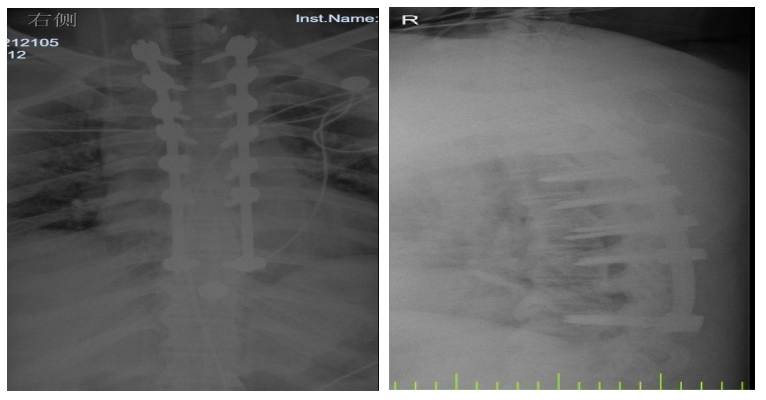

入院后,國(guó)文醫(yī)院骨科迅速組織多名專家會(huì)診,并為吳先生完善了頸椎及胸椎的 MRI 檢查。結(jié)果顯示,吳先生的頸椎及胸椎多階段嚴(yán)重椎管狹窄,脊髓壓迫超過(guò) 50%,情況十分危急。經(jīng)過(guò)骨科專家團(tuán)隊(duì)的綜合會(huì)診及評(píng)估,最終為他制定了一套個(gè)性化的治療方案,包括頸椎后路單開(kāi)門椎管減壓頸椎融合內(nèi)固定術(shù),以及胸椎間盤切除伴椎管減壓胸椎植骨融合內(nèi)固定術(shù)。在完善術(shù)前檢查、確認(rèn)無(wú)手術(shù)禁忌后,骨科主任呂國(guó)福如期為吳先生實(shí)施了手術(shù)。

手術(shù)涉及頸椎及胸椎多個(gè)階段,操作難度極大。專家團(tuán)隊(duì)采用 “蠶食法” 減壓,分塊去除增生韌帶,最大程度減少對(duì)脊髓的損傷;同時(shí)運(yùn)用椎弓根螺釘固定技術(shù),確保手術(shù)部位的穩(wěn)定性。